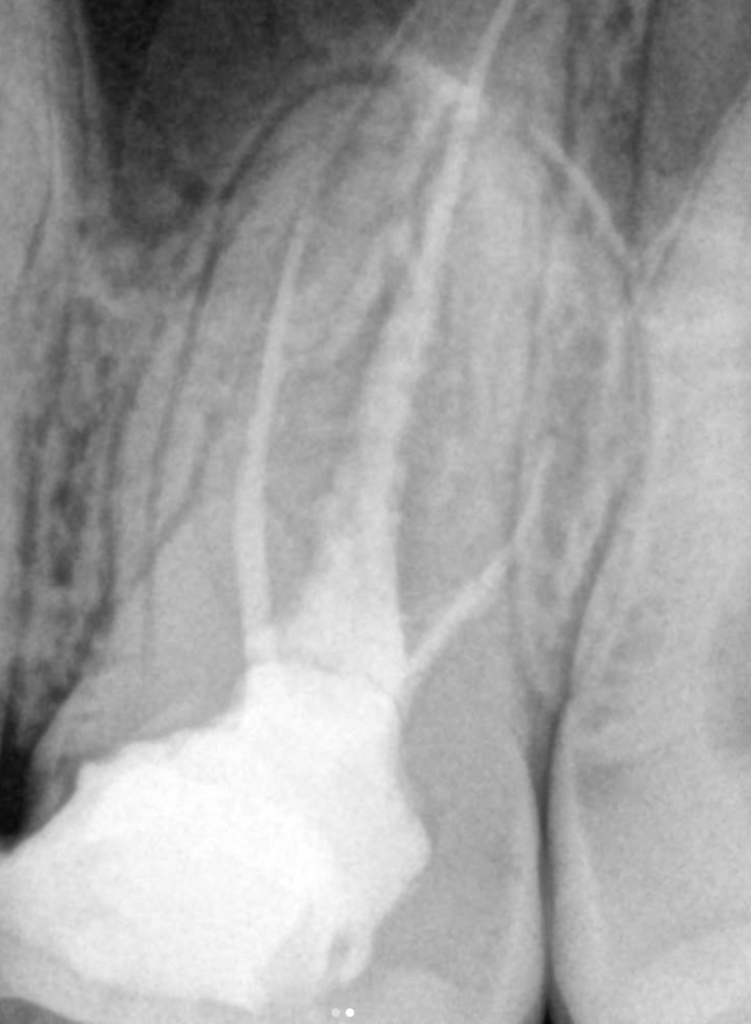

❗️Jeśli ząb był już leczony endodontycznie, ale występują dolegliwości, nie zawsze musi oznaczać to usunięcia zęba❗️

Często udaje się uratować zęba🦷✅